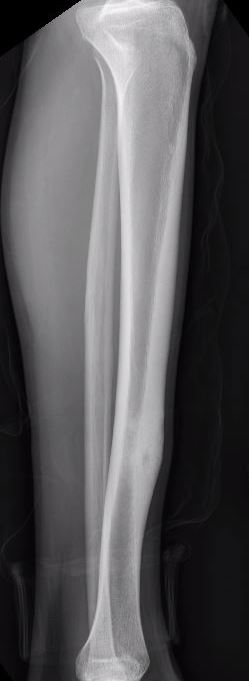

X-ray

Sclerotic bone

Osteoid osteoma femur